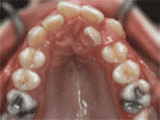

第四种

牙列拥挤,牙槽骨过窄,牙齿没有足够空间,只好前后左右高低上下乱长,经过矫正后的牙齿是这样的